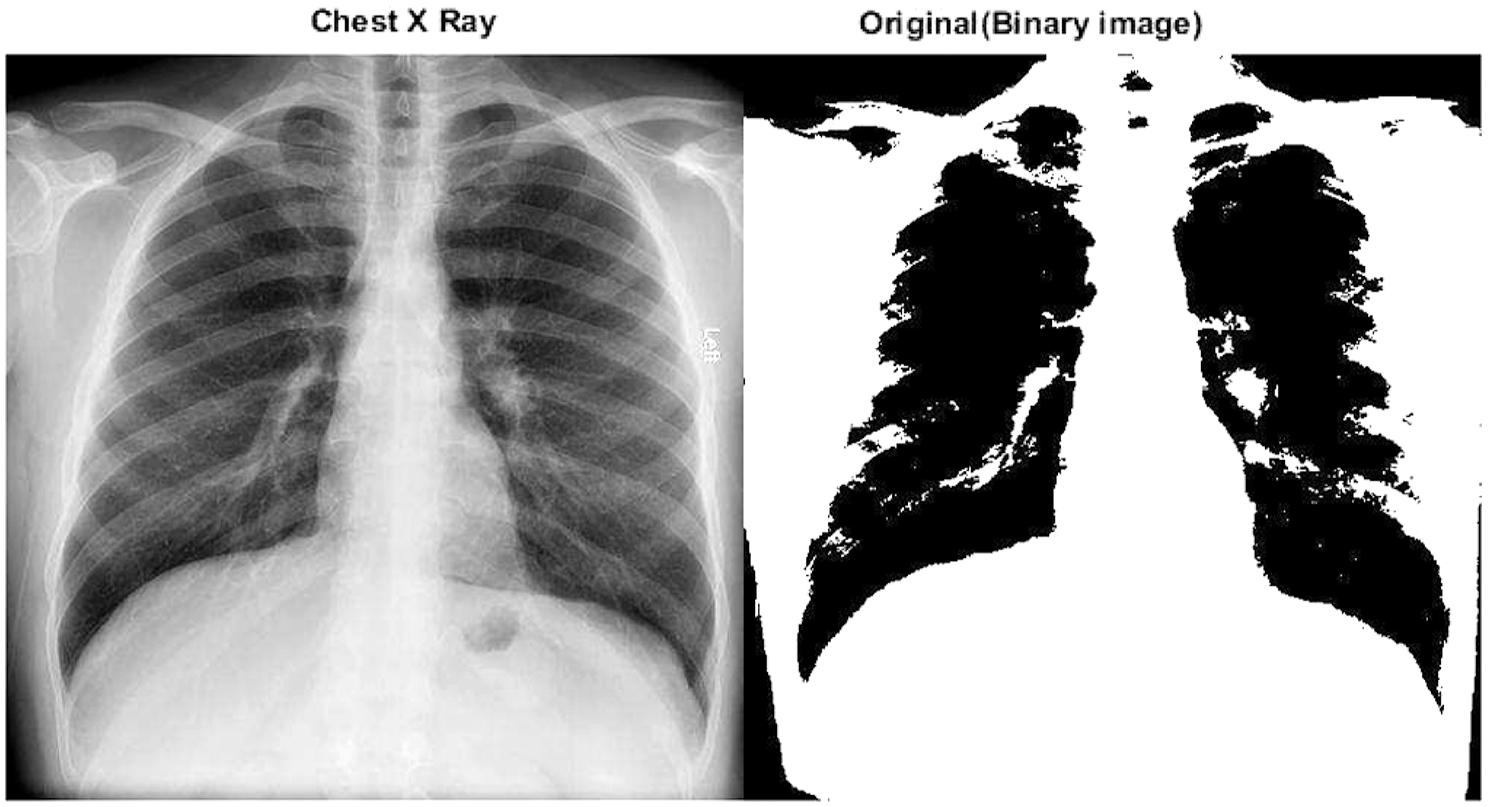

Figs. 10 and 11 show two typical chest X-ray images, one from a health subject and another from a COVID-19 patient with ARDS.

Figure 10: A chest X-ray of a COVID-19 patient with ARDS and the corresponding binary image in